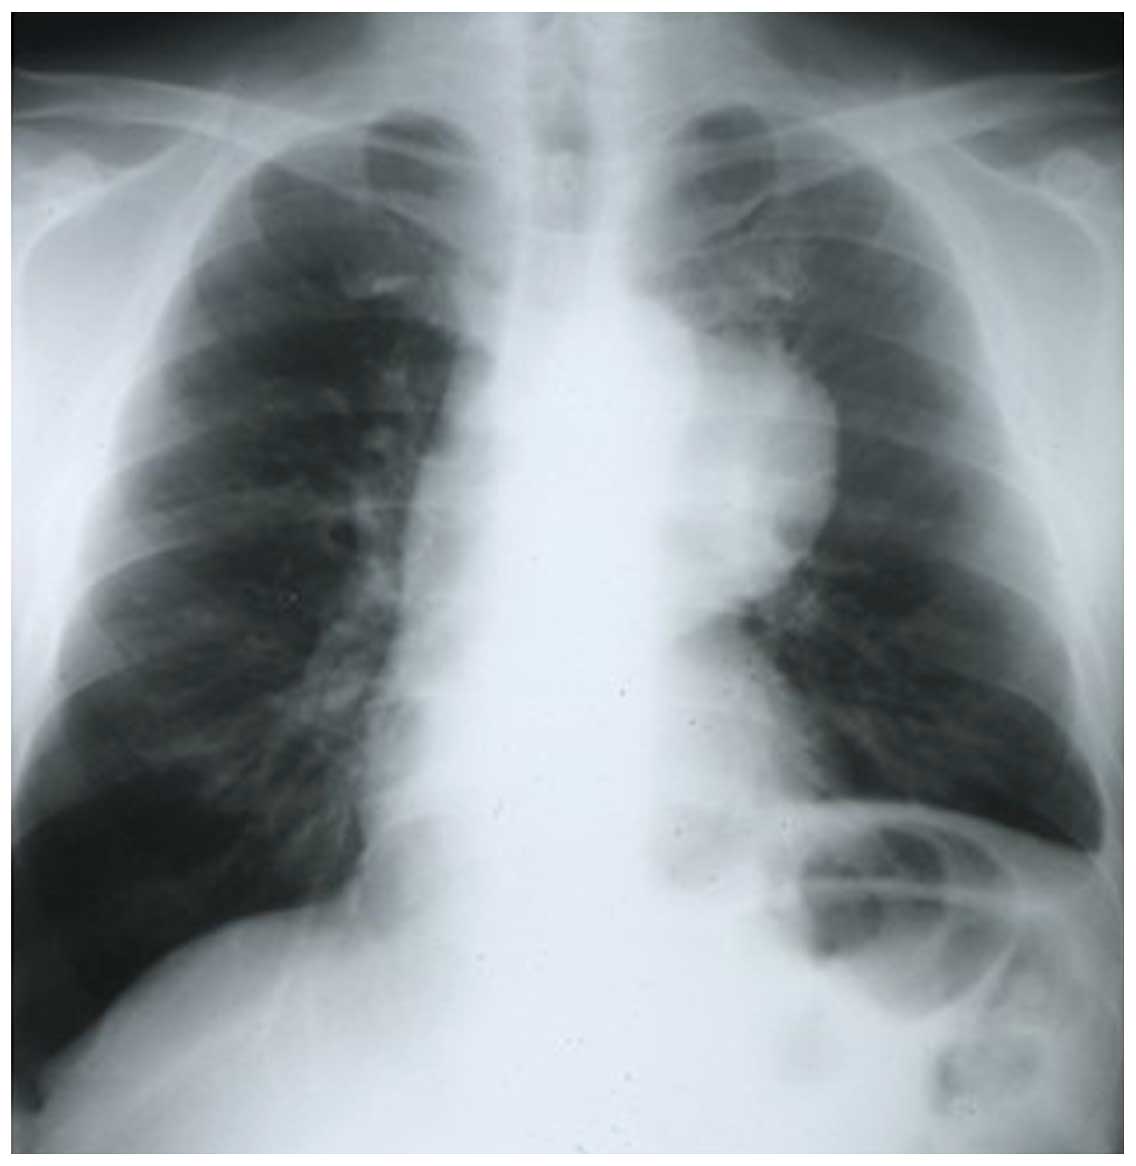

Thymus Chest X Ray

from mavink.com